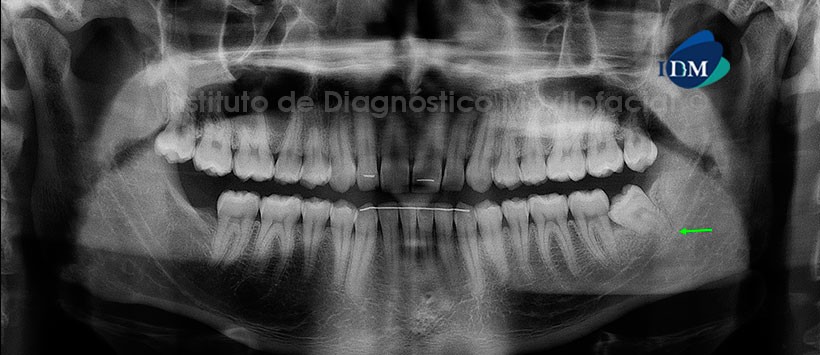

Paciente masculino de 25 años de edad que es referido para la evaluación de las terceras molares. La radiografía panorámica nos muestra a la pieza 38 en posición mesioangulada e impactada contra la superficie cervicodistal de la pieza 37. Así mismo, se observa que el tercio apical radicular está proyectado sobre el conducto dentario inferior, llevando a la sospecha de un compromiso de este último. Por otro lado, se evidencia la neumatización alveolar de los senos maxilares, dispositivos radiopacos de fijación en el sector anterior y la ausencia de la pieza 48 (Fig. 1).